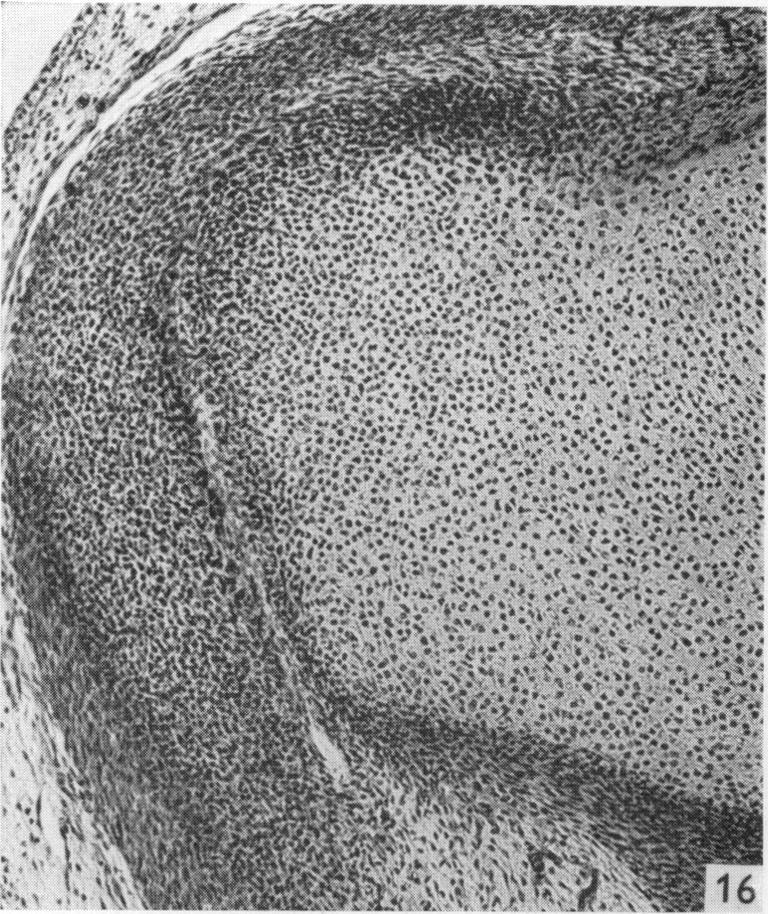

The early development of the knee joint in staged human embryos.

J Anat. 1968 Jan;102(Pt 2):289-99.